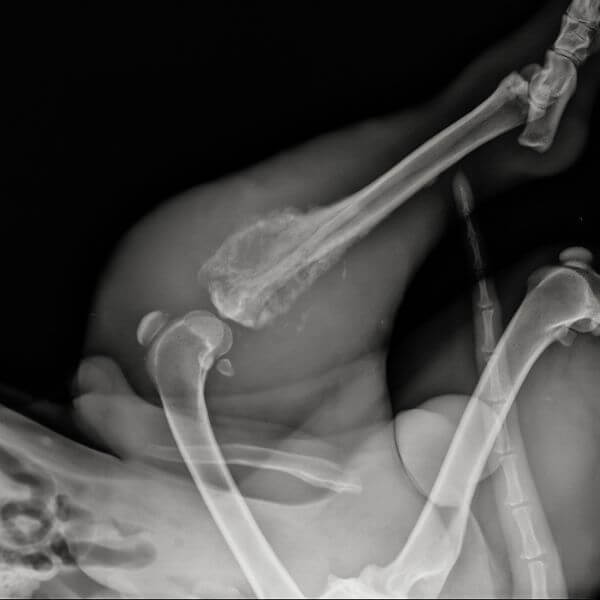

The ulna, radius, femur, and tibia – some of the longest bones in a large dog’s body – are the areas most commonly affected by osteosarcoma, as osteosarcoma in dogs is more likely to affect the limbs, as opposed to the skull, spine, or ribcage. In addition to the potential for tumor growth during a dog’s early development, large dogs also carry a higher risk for the development of osteosarcoma due to the additional strain that is placed on these long bones due to the dog’s size and stature. This strain can often result in microfractures, or small cracks in a dog’s bones, that can lead to decreased bone health and stability, as well as malignant changes in a dog’s overall bone tissue.

If your dog is showing signs such as limping, swelling, or persistent leg pain, scheduling a veterinary checkup is the best course of action. For pet owners in Savannah, Georgia, our experienced team at Port City Animal Hospital can perform a thorough exam and diagnostic testing to determine whether your dog’s limp is caused by injury, arthritis, or a more serious condition such as bone cancer. Veterinarians may use X-rays, physical exams, biopsies, and sometimes CT scans to confirm the presence of a tumor and assess how far it has grown or spread.